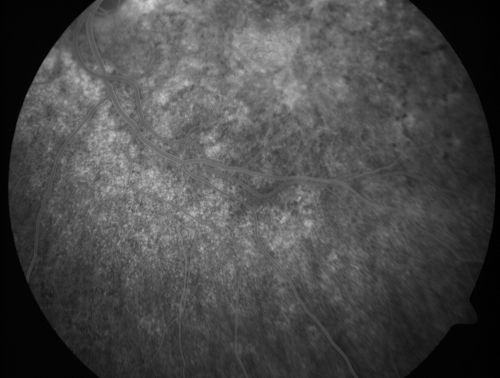

Basal Laminar Drusen - Cuticular Drusen - Equatorial Drusen - 70 Year Old Woman

70 year old woman has had macular drusen since her thirties and she said her sister has a similar problem.  Recently the vision in the left eye has substantially declined. OD 20/16, OS 10/200.